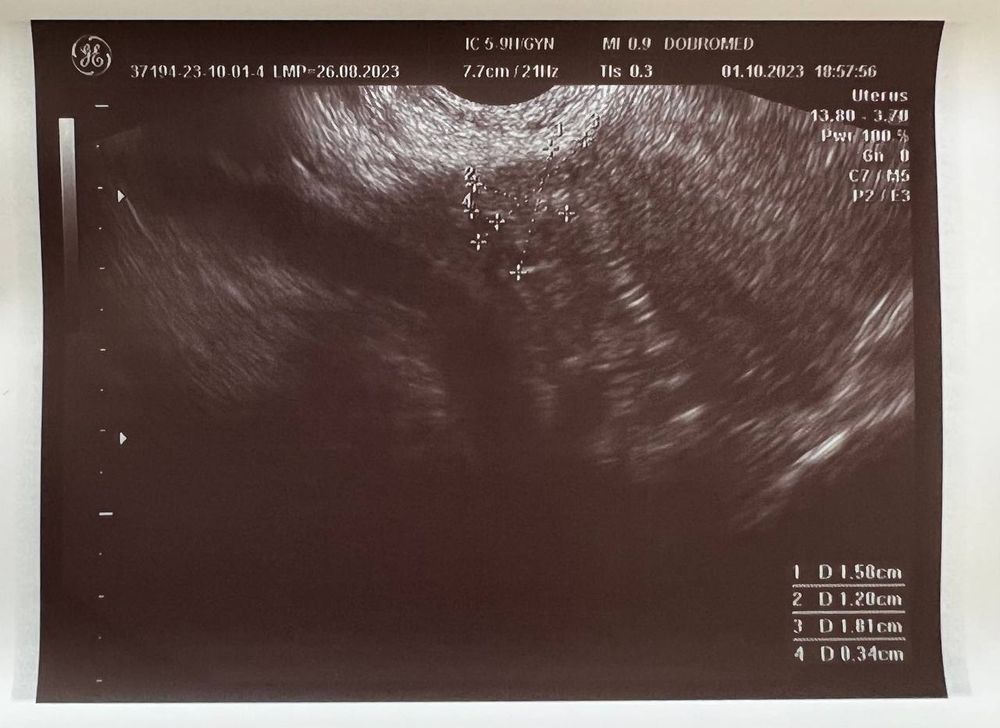

Вчера (1 октября) сходила на УЗИ, беременность подтвердили, маточная.

Но не видно желтое тело, и мутное содержимое плодного яйца (как она сказала). Меня напугала очень узистка... мол, может быть замершая беременность.

Если есть специалисты тут - пожалуйста, посмотрите снимок

Ниже фото заключения и УЗИ: